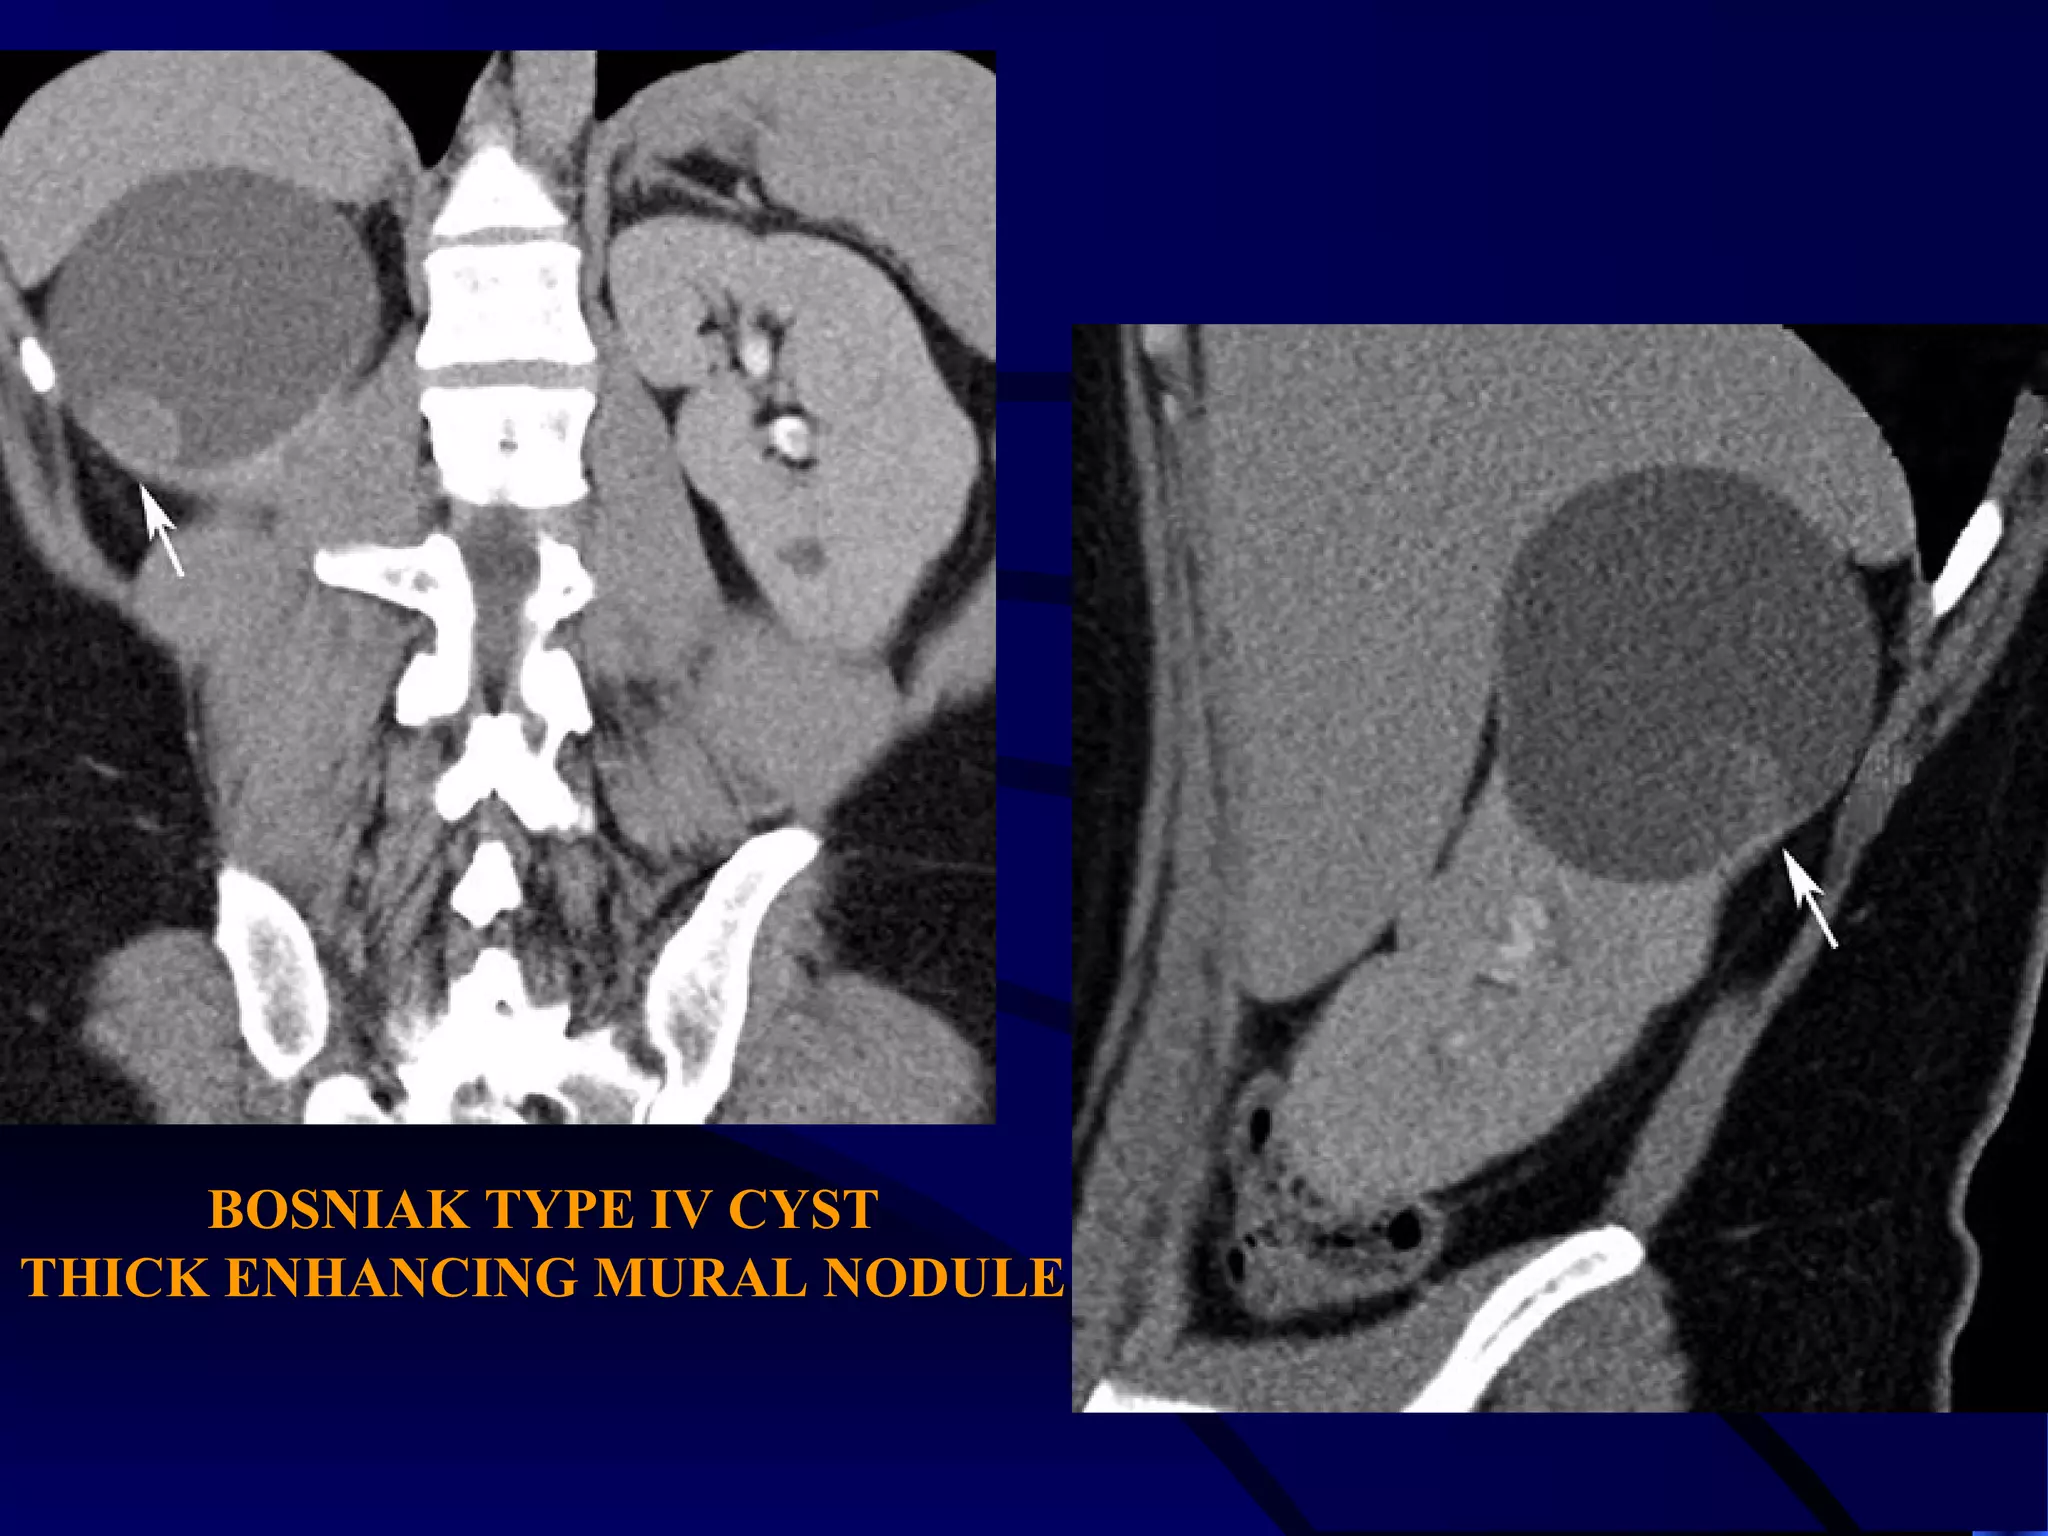

CASE (7)

BOSNIAK TYPE IV CYST

THICK ENHANCING MURAL NODULE